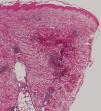

If eosinophilia is absent, a skin biopsy is quite helpful. The amount of eosinophils is variable, and although not pathognomonic, their presence in the subcutaneous tissue (eosinophilic panniculitis) is highly characteristic (Figure 6). The infiltrate, however, may be limited to the dermis. Flame figures can be seen in gnathostomiasis and, as such, should not be considered characteristic of Wells syndrome only (eosinophilic cellulitis) (Figure 7).